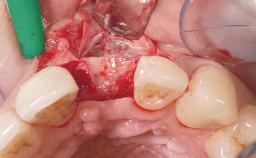

Late Flapless Placement of an Implant in a Maxillary Left Central Incisor Site

Bone Augmentation Horizontal|Staged

Augmentation Materials Xenogenous|Membrane

Soft Tissue Grafting Simultaneous